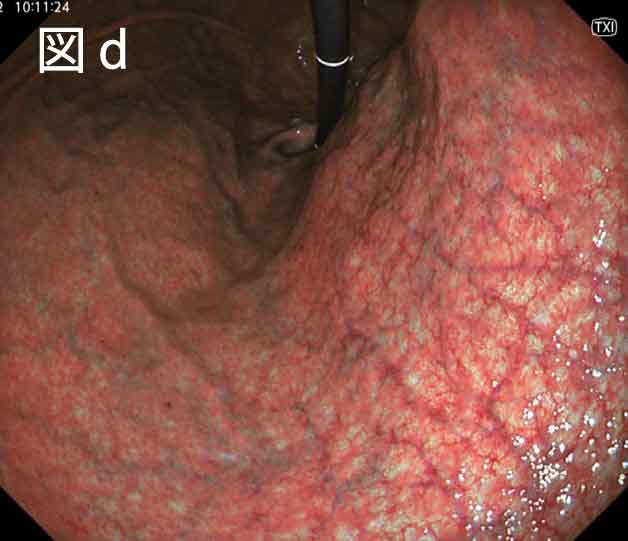

このジレンマを解消すべく2020年3月に登場したのが、次世代細径内視鏡GIF-1200Nです。GIF-1200N はGIF-XP290Nを超える明るくノイズの少ないハイビジョン高精細画像で観察ができ、一方で先端部を太くすることなく5.4mmと極細径を維持しつつ挿入時の苦痛を犠牲にすることはありません。実際に従来の細径内視鏡では良い意味ではコシがあったのですが、咽頭から梨状窩を超える際にはやや硬さを感じていましたが、GIF-1200Nの経鼻での挿入時にはそのような硬さを感じることはなく、非常に滑らかに挿入が可能です。さらに、GIF-XP290Nまでの細径内視鏡では、胃噴門部の反転観察をする際に、アップアングルを最大にしても不十分に感じることがあり、左右アングルの共同で何とか観察をすることもありました。GIF-1200Nではカタログ上のアップアングル角は210度従来と変更はありませんが先端部分以外の剛性を変更したことにより反転操作の視認性が向上していると感じました (図a)。このようにGIF-1200Nを使用することにより、内視鏡スクリーニング検査において求められる低侵襲および高精度の検査が可能となったと言えると感じています。